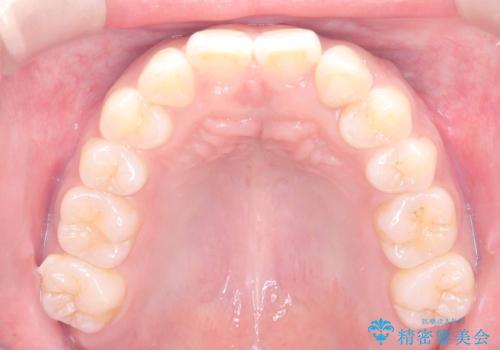

- 「歯の捻じれとがたつき」を主訴に来院された患者様です。

軽度な捻転と叢生だったため、インビザラインのモデレートで治療を行いわずか半年で治療を終える事が出来ました!

目立たないマウスピース矯正【インビザライン】を使用し、

わずか6ヵ月で歯並びがキレイに整いました!

矯正後は、リテーナー(保定装置)を使用し後戻りを防止中です。